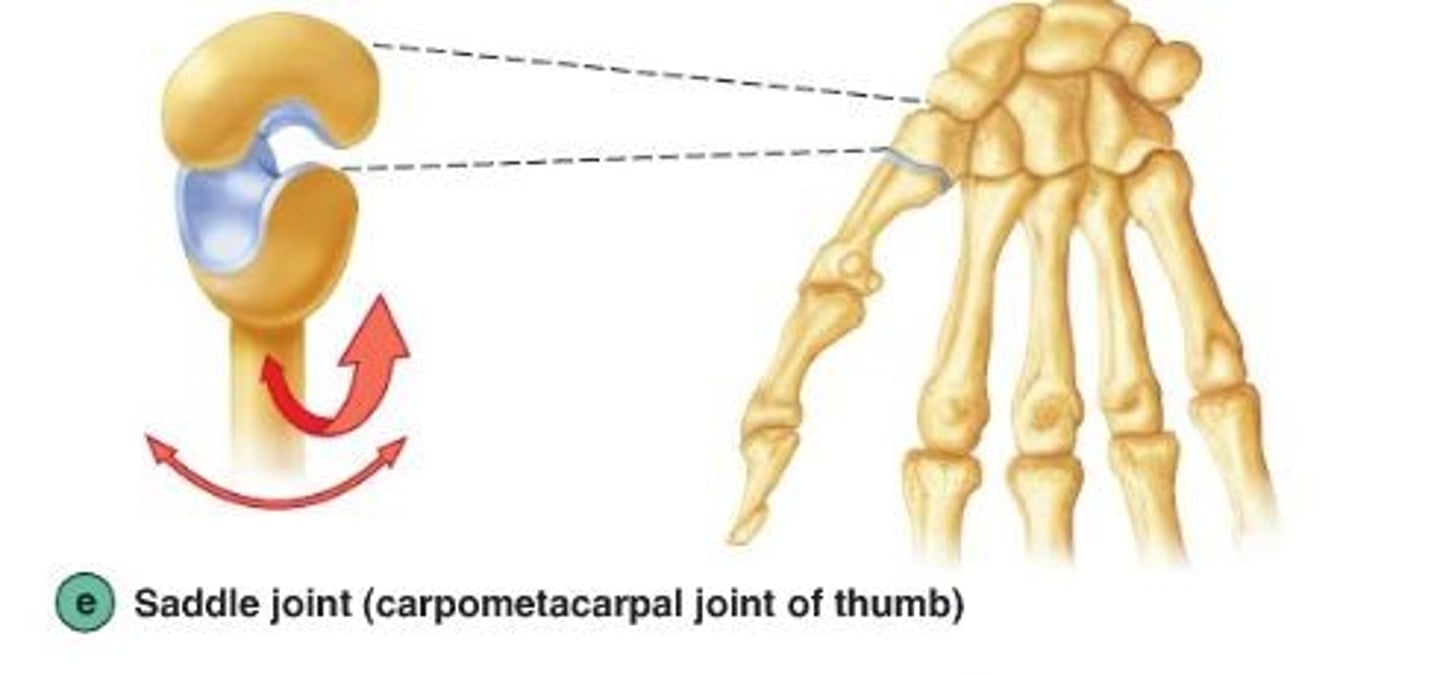

Saddle synovial joint

allow movement around two axes that are at right angles to each other

-articular surfaces are saddle shaped permitting flexion, extension, abduction, adduction, and circumduction

ex: carpometacarpal joint of the thumb